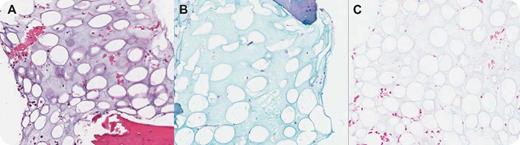

A 69-year-old man developed fatigue, dyspnea, expanding girth, night sweats, and weight loss. On examination he had ascites and peripheral edema. He had normocytic anemia (hemoglobin 8.2 g/dL), normal white count, minimal lymphopenia, normal platelet count, and a normal peripheral smear. Lactate dehydrogenase was 7500 u/L and serum proteins noted with mild hypoalbuminemia and marked hypogammaglobulinemia (0.24 g/dL). The ascitic fluid showed lymphoma cells. Computed tomography showed pleural effusions, ascites, and abdominal and mediastinal masses. An abdominal lymph node biopsy made the diagnosis of B-cell lymphoma, unclassifiable, with features intermediate between diffuse large B-cell lymphoma and Burkitt lymphoma. The bone marrow aspirate revealed trilineage hematopoiesis and poorly stained acellular material. The bone marrow biopsy showed extensive gelatinous transformation characterized by extracellular deposits of amorphous, smooth, gelatinous material (panel A; HE), rich in hyaluronic acid that was Alcian Blue stain positive (panel B). After treatment with hyaluronidase (panel C; Alcian Blue with Hyaluronidase) the stain became negative. Combination chemotherapy resulted in clinical remission. No posttherapy bone marrow biopsy has been performed.

Gelatinous transformation or serous fat atrophy has been described in cancer-related cachexia and end-stage renal disease. It has since been noted with myxedema, anorexia nervosa, infections, and malignant neoplasms, including lymphoma. Currently it is mostly noted in anorexia nervosa, predominantly in marathon runners, and in end-stage AIDS. Gelatinous transformation of the bone marrow is uncommon but it can be identified by radiologists on magnetic resonance imaging (MRI). There were no MRIs performed on this patient.